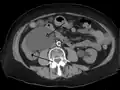

- Urine jets[14]